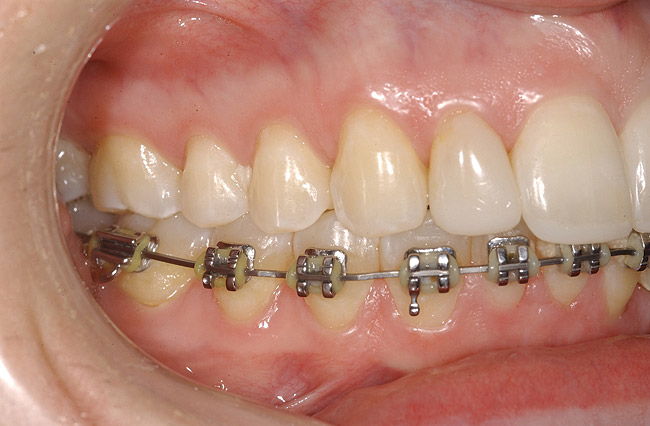

Figure 14  Interproximal bone present at teeth Nos. 21 and 22, postorthodontics.

Figure 14

Following the first goal of orthodontia—moving tooth No. 22 to a proper functional and anatomical position—a periodontal reevaluation was performed, demonstrating an improvement in short- and long-term tooth prognosis. At this time, the decision was made to abort continual extrusion of teeth Nos. 21 and 22, although some attachment level discrepancy remained between Nos. 21 and 22 (Figure 14). Implant diagnostics ensued and included mounted study models and a diagnostic wax-up. A scanning appliance was created to demonstrate the desired prosthetic outcome requirements, and the patient was referred for computed tomography (CT) scans. CT scan assessment demonstrated successful orthodontically directed GBR to allow implant placement (Figure 15 through Figure 16). Only minor GBR therapy would be needed and could be accomplished simultaneously with implant installation. Guided implant placement occurred, using an open flap approach (Figure 17). During surgery, root dehiscences were noted on teeth Nos. 21, 22, 24, and 25, as well as the anticipated dehiscence following implant placement at No. 23 (Figure 18). A positioning reference (index) was secured after implant placement to facilitate a provisional prosthesis at stage II surgery. Cortical perforations then were placed adjacent to the implant to encourage angiogenesis (Figure 18), and mineralized freeze-dried bone allograft enhanced with platelet-derived growth factor was placed over the dehiscences for purposes of guided tissue regeneration and GPR (Figure 19). A highly resorbable collagen membrane was placed to stabilize the allograft. The flap was coronally repositioned, and primary-intention wound healing was achieved (Figure 20 and Figure 21). Following 4 months of stage I surgery, implant uncovery and immediate provisionalization was performed in conjunction with connective tissue grafting. Final orthodontic tooth movement then ensued, using the implant as anchorage to optimize end-tooth movements, interroot separation, and the cuspid-protected occlusal scheme. A final impression then was secured, and a zirconia abutment (Figure 22) with an all-ceramic restoration was fabricated for the prosthetic phase completion of No. 23 (Figure 23] through Figure 25).